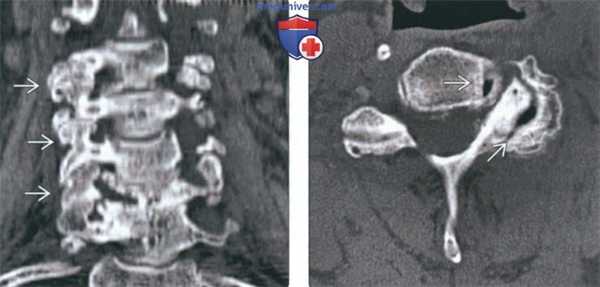

(Слева) На корональной КТ без КУ определяется тяжелая многоуровневая гипертрофическая дегенеративная артропатия дугоотростчатых суставов со стенозом межпозвонковых отверстий.

(Справа) На аксиальной КТ без КУ определяется тяжелая левосторонняя дегенеративная артропатия дугоотростчатого сустава со стенозом межпозвонкового отверстия. Определяется вакуум - феномен дугоотростчатого сустава и унковертебрального сустава.

(Слева) КТ, фронтальный срез: признаки выраженной многоуровневой дегенеративной гипертрофической артропатии дугоотростчатых суставов с фораминальным стенозом.

(Справа) КТ, аксиальный срез: признаки выраженного дегенеративного поражения левого дугоотростчатого сустава и фораминального стеноза. В полости дугоотростчатого и унковертебрального сустава отмечается «феномен вакуума».